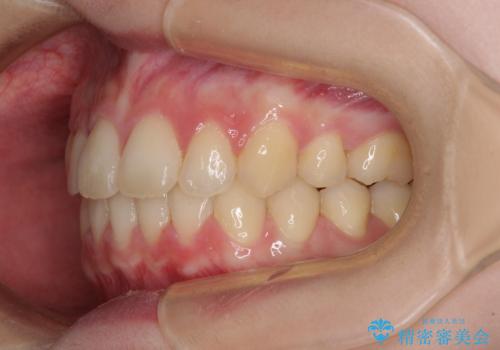

- 口元の突出感を気にして来院された患者様です。

左右ともに上顎奥歯が外を向き、下顎奥歯が内側に倒れているシザーズバイトであったため、補助装置により改善することとしました。

上下の咬み合わせは、下顎に対して上顎が相対的に前方にあったため、奥歯のシザーズバイト改善後に上顎左右第一小臼歯2本を抜歯し、上顎前突を改善していくこととしました。

左側の咬み合わせと上下正中の位置をコントロールするために時間がかかりましたが、事前に思い描いた通りの歯列に整い、患者様には大変満足していただきました。